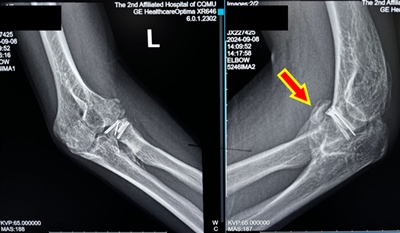

左图:术前肘关节X线片示大量异位骨化形成

右图:肘关节CT显示,异位骨化广泛分布于肱尺关节、肱桡关节